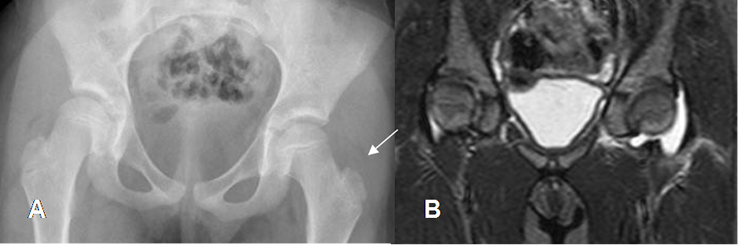

En las etapas subaguda y crónica, se produce erosión y destrucción ósea. Puede encontrarse también reacción perióstica en láminas. (16). (Fig 64 A, 64 B, 64 C y 64 D).

En la fase final hay destrucción articular, con anquilosis y edema de tejidos blandos. (16). (Fig 65 A y B).

Fig 64 A. Artritis séptica.

Rx AP. Disminución del 4º espacio metacarpofalángico y pérdida en la nitidez de los contornos en la cabeza del metacarpiano, por artritis séptica.